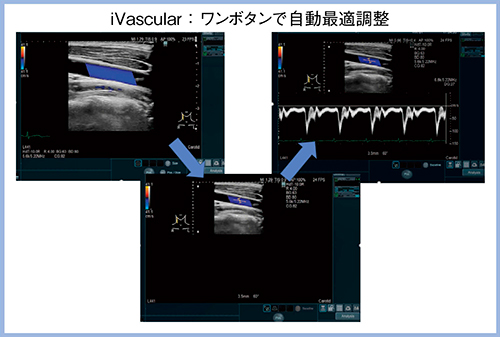

“iVascular”は,カラードプラの関心領域,カーソルの位置・幅・補正角度の4つの設定がワンボタンで自動的に調節される機能で,理想的なパルス波形が描出される(図4)。Protocol Assistantと組み合わせることで検査時間を大幅に短縮できる非常に優れた機能である。

図4 iVascularの表示画面